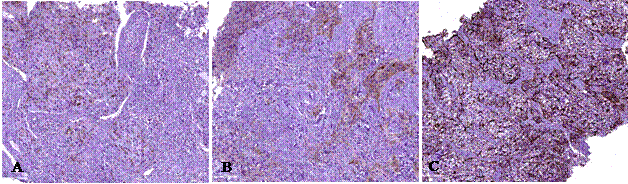

Высокая степень TILs выявлена в 12,5% случаев pCR, средняя – в 12,5% и низкая – в 75,0% (рис.1). В случаях не-pCR не было выявлено высокой степени инфильтрации TILs, средняя и низкая степени были отмечены у 44,4 и 55,6% соответственно. Однако не выявлено статистически значимых различий (р>0,05, U-критерийМанна – Уитни) между уровнем инфильтрации TILs в группах pCR и не-pCR.

Рис.1. Морфологическое исследование биоптатов рака молочной железы. Окраска гем.-эозин. Общ. ув. х 200. Степени инфильтрации TILs: А) высокая, B) средняя, С) низкая. Примечание: составлен авторами по результатам данного исследования